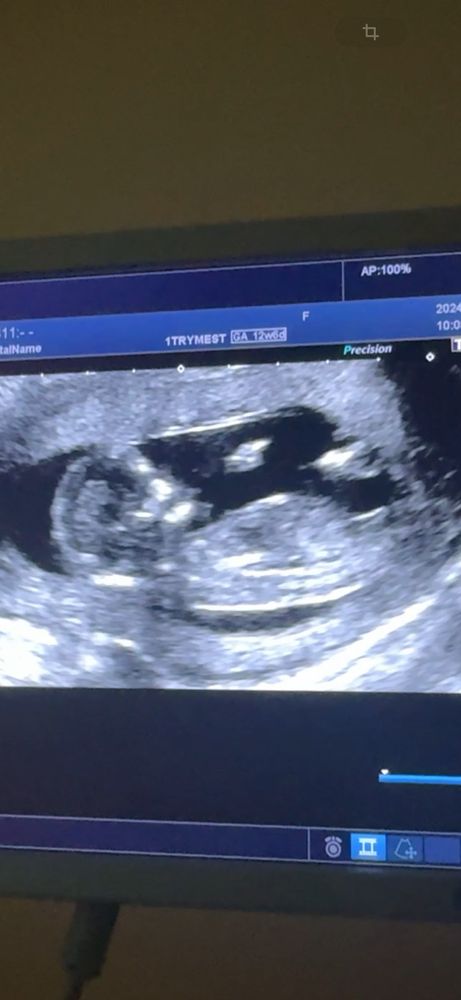

Пол ребенка 1 скрининг

Девочка , угол маленький между спинкой и половым бугорком , почти параллельны. При мальчике большой угол

У дочки такой же половой бугорок был на первом скрининге

Девочка, половой бугорок параллельно спинке